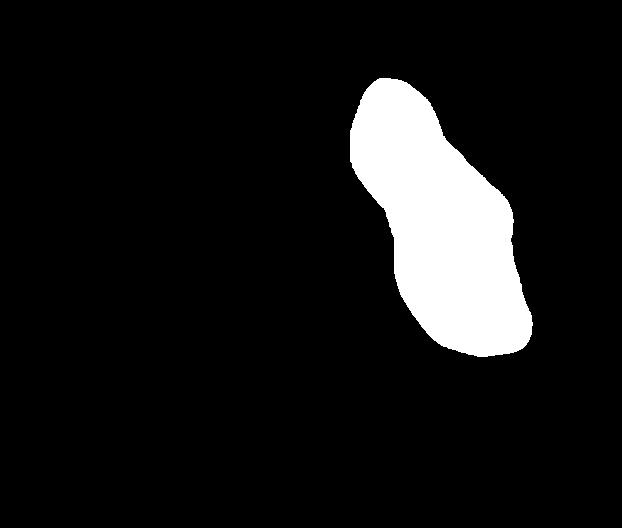

As part of the EndoCV2021 challenge (https://endocv2021.grand-challenge.org/), we were tasked with creating machine learning models that automatically segment polyps [11, 12, 13] in video frames collected from real-world endoscopies. This is a complex task as polyps come in various shapes and sizes, where some (e.g., flat lesions) are barely detectable by even the most experienced endoscopists. Figure 1 shows some of the more difficult examples taken from EndoCV’s development dataset [10] provided by the challenge organizers. The challenge presented two separate tasks, the detection generalization challenge and the segmentation generalization challenge. We participated in the segmentation generalization challenge, where we achieved the best results among 13 other competitors in both rounds. The code for the experiments presented in this paper is available on GitHub111https://github.com/vlbthambawita/divergent-nets.

Figure 4 shows some example masks predicted by our best performing model (DivergentNets) together with masks produced by the intermediate models. We see that each intermediate model learns slightly different features, making an overall more precise segmentation mask when combined. For example, the first row of Figure 4 shows the predicted masks and ground truth of a large polyp. We see that each model predicts slightly different masks for the same input and that TriUNet over-estimates the size of the polyp. After averaging the predicted masks for DivergentNets’ final output, this area is smoothed out by the predictions from the other intermediate models.